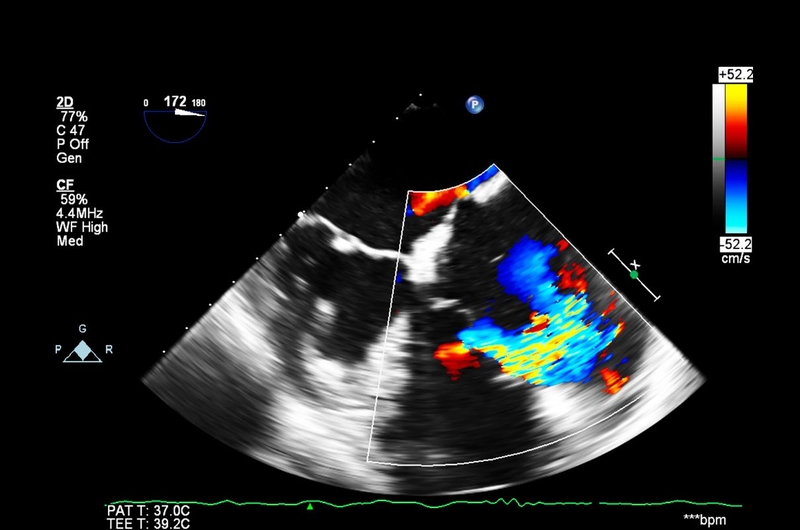

Siêu âm tim đặc biệt hiệu quả trong trường hợp nhồi máu cơ tim có block nhánh hay nhồi máu cơ tim không Q. Trên siêu âm, các hình ảnh rối loạn vận động vùng sẽ cho biết vị trí nhồi máu. Siêu âm cũng giúp đánh giá các biến chứng như: Tràn dịch màng tim, buồng tim có huyết khối, đứt dây chằng làm hở van tim, thông liên thất do thủng vách tim.